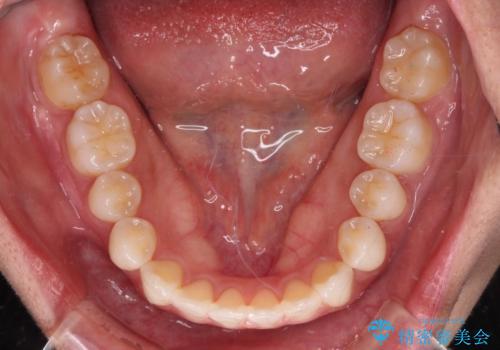

- 前に出ている上顎前歯が気になるとのことで来院された患者様です。

インビザラインを用い、IPR(歯と歯の間を削る)と歯列全体を後方に移動させることで、可能な限り前歯の突出感を改善することとしました。

元々の歯列も整っており、横顔の印象の出っ歯ではなかったため、仕上がりに満足できない可能性があると心配しておりましたが、口が閉じやすくなり、患者様には大変満足していただきました。